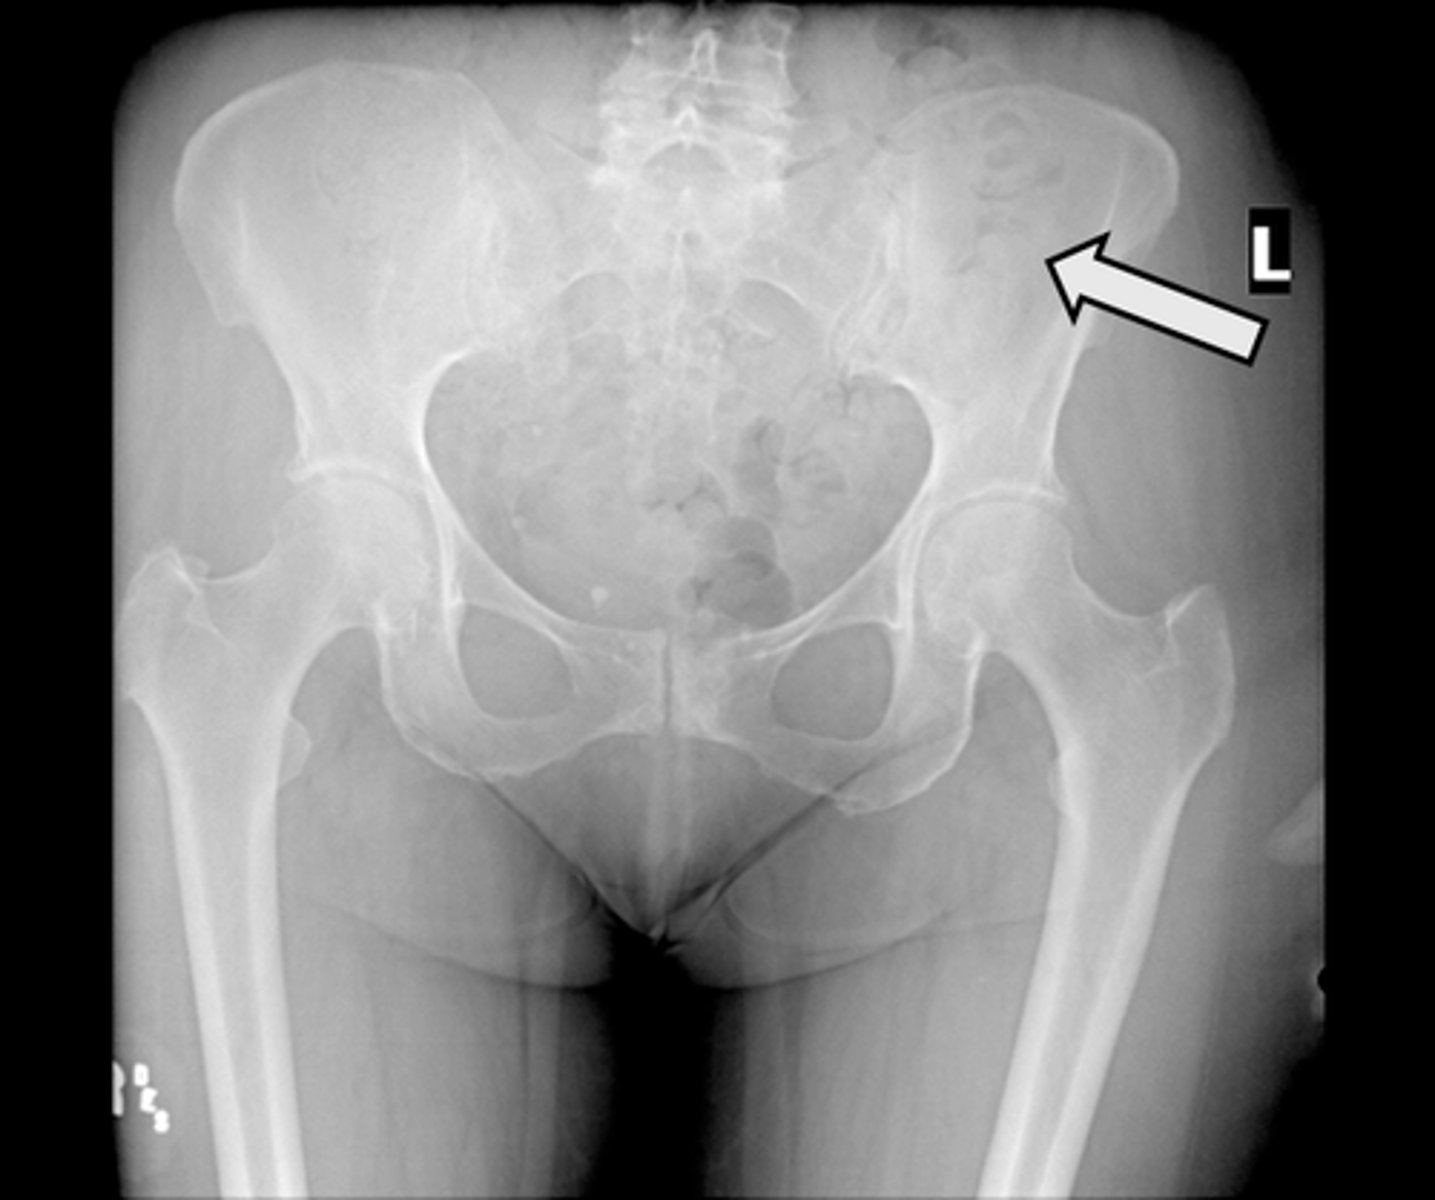

AP pelvis

What is the image?

L acetabulum

What is indicated in the image?

L anterior superior iliac spine (ASIS)

L ilium

L ischial tuberosity

L obturator foramen

L sacroiliac joint

L superior ramus of pubis

R acetabulum

R anterior superior iliac spine (ASIS)

R ilium

R ischial tuberosity

R obturator foramen

R sacroiliac joint

R superior ramus of pubis

Sacrum